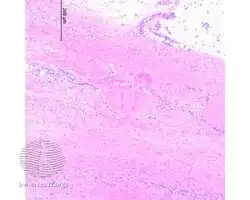

Eosinophilic fasciitis/pathology